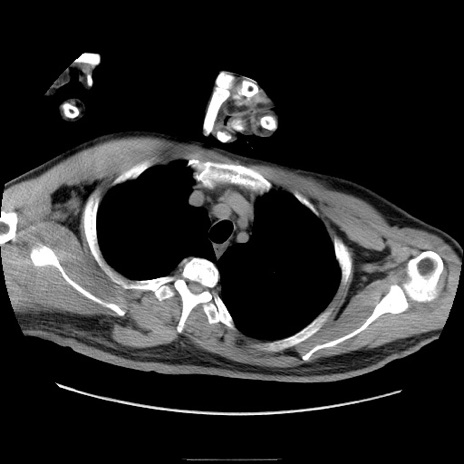

症例22(横断像)

【症例】50歳代男性

【主訴】腹痛

【現病歴】AVMからの被殻出血のため回復期リハ病棟入院中。 本日午後3時頃急に下腹部痛が出現した。

【既往歴】AVM、被殻出血、虫垂炎、高血圧

【身体所見】意識晴明、左半身不全麻痺、会話の理解は良好、36.5°C、腹部:膨隆、全体に板状硬、下腹部正中に圧痛点あり、反跳痛-、筋性防御不明、右下腹部にope scar

【データ】WBC 9400、CRP 0.06